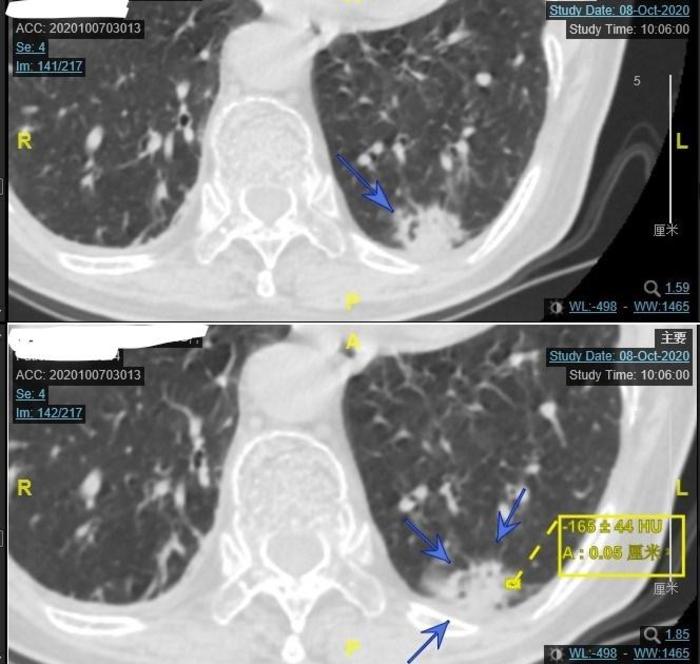

上图可见蓝色箭头指示的2018年3月左上肺实性结节,大小约9毫米,距离肋骨处的胸膜较近。当时也认为是慢性炎症。

上图为今年9月份住院后的CT,由两张CT组成。上面的CT的蓝色 箭头指向的是左上肺实性结节。下面的CT黄色箭头指向的是这个结节紧贴斜裂,好像比两年半前大了1毫米,差别不大。